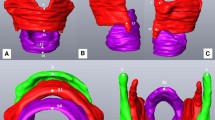

Figure 2 shows hyoid bone density by age group for females, males, and both sexes combined. In the three adult age groups, females had lower bone density than males, with the largest difference occurring in older adults. In the pediatric age group, there was no significant difference between male and female hyoid bone density (t(44) = −0.22, p = .83). The pediatric age group was excluded from the 2-way and 3-way ANOVA models below because bone density increases throughout childhood and adolescence [29, 30] and because no partial fusion or fusion occurred in this age group.

Hyoid bone density (mean intensity in HU) by sex and age group with standard error bars. Lines with asterisks (*) indicate significant post hoc differences (p < 0.05 Tukey-HSD) for sex and age in the 2- and 3-way ANOVA models. Sex and age groups include all fusion categories. The pediatric age group was not included in ANOVA models

Figure 3 shows hyoid bone density by fusion category and age group. The highest hyoid bone density occurred in young adults with partial or unilateral fusion while the lowest bone density occurred in adults with bilateral fusion.

Hyoid bone density (mean intensity in HU) by fusion category and age group with standard error bars. Lines and asterisks (*) indicate significant post hoc differences (p < .05 Tukey-HSD) for the Age × Fusion interaction in the 3-way ANOVA model. Fusion category is based on fusion rank on both right and left sides (given no significant differences in laterality) and age and fusion groups include both sexes (given no significant Sex × Age × Fusion interaction). The pediatric age group was not included in the ANOVA model

Three-way ANOVA models were used to examine the association of bone density with fusion category, sex, and (adult) age group. As in the two-way ANOVA model, sex (F(1,76) = 9.86, p = .002) and age group (F(2,76) = 5.08, p = 0.009) were significant main effects. There were significant differences in density between males and females (Female = 265 HU, Male = 300 HU, p = .0024) and young adult and older adult age groups (Older adult = 257 HU, Young adult = 303 HU, p = .007) in post hoc comparisons. Fusion category was not a significant main effect (F(2,76) = 1.38, p = .26); however, the Age Group x Fusion Category interaction was significant (F(4,76) = 2.66, p = .039), indicating that the relationship between bone density and fusion category varied by age. In post hoc comparisons, young adults with partial or unilateral fusion (LS mean = 331.21 HU) and middle-aged adults with bilateral fusion (LS mean = 318.7 HU), had significantly greater bone density than older adults with bilateral fusion (233.74 HU; p values = .017 and .006 respectively; see Fig. 3). There were no significant differences in bone density by fusion category within age groups. All other 2- and 3-way interactions were not significant and were not included in the final model.